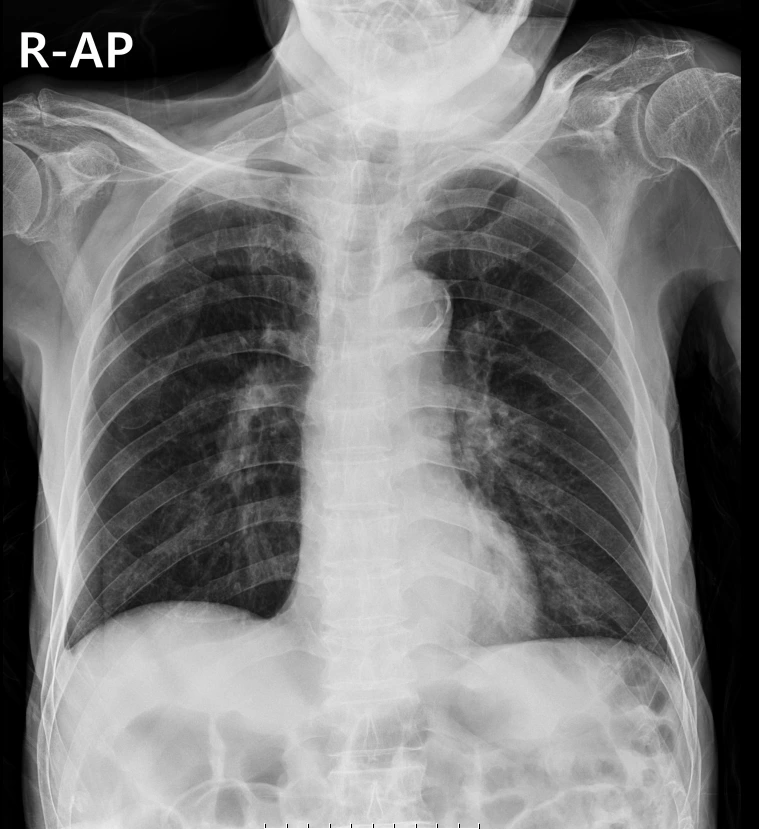

하지만 이 세 가지 중에 하나라도 충족이 안되는 경우는 무조건 Chest X-ray를 찍어야 하는데, '어떻게 이럴 수가 있지 '하는 생각이 저절로 들게 하는 결과물들이 종종 나온다.

위 사진을 보면 식도 중간에서 비위관(L-tube)가 꼬여있다.

입 밖으로 나오지도 않았고 70cm가 넘게 들어갔을 경우에는 이렇게 식도 중간에 꼬인 경우가 많다.

그 좁은 식도 안에서 어떻게 저런 식으로 튜브가 꼬였을까?

비위관의 끝은 나름 단단한 고무로 되어있어서 끝은 늘 일직선으로 되어있다. 그래서 더더욱 아래로 내려갔다가 다시 위로 올라오기가 쉽지 않은데, 식도까지 내려갔다가 다시 올라오는 경우가 흔하다는 사실이 참 신기하다.

식도 안에서 일어나는 일을 당최 볼 방법이 없으니 그저 비위관이 혼자 몸을 배배 꼬며 미끌미끌한 식도 벽에 머리를 처박고 그 반발력을 이용해 위로 다시 올라왔겠거니 하며 상상할 뿐이다.